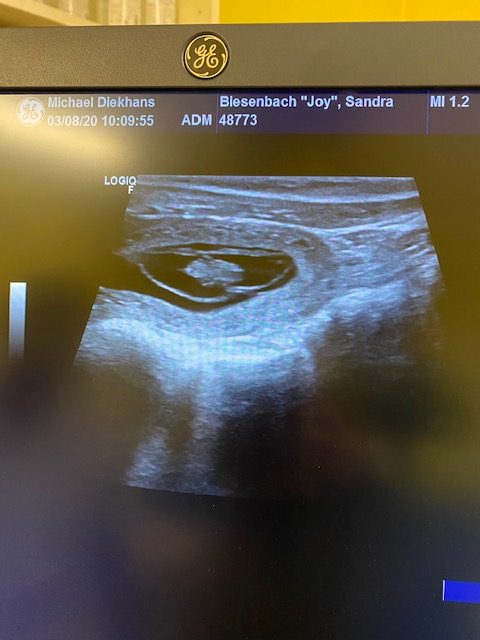

Heute war ich mit Joy beim Ultraschall. Wir freuen uns riesig über das Ergebnis: Joy ist trächtig! Nun heißt es wieder warten, was uns doch so sehr schwer fällt…Zeit kann sehr langsam vergehen 😉

Der Geburtstermin unseres M-Wurfs wird ca. der 09.09.2020 sein!